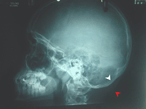

Primitive synovial sarcoma of suboccipital region in child

Ploutarchos Karydakis and others

Journal of Surgical Case Reports, Volume 2018, Issue 10, October 2018, rjy286, https://doi.org/10.1093/jscr/rjy286